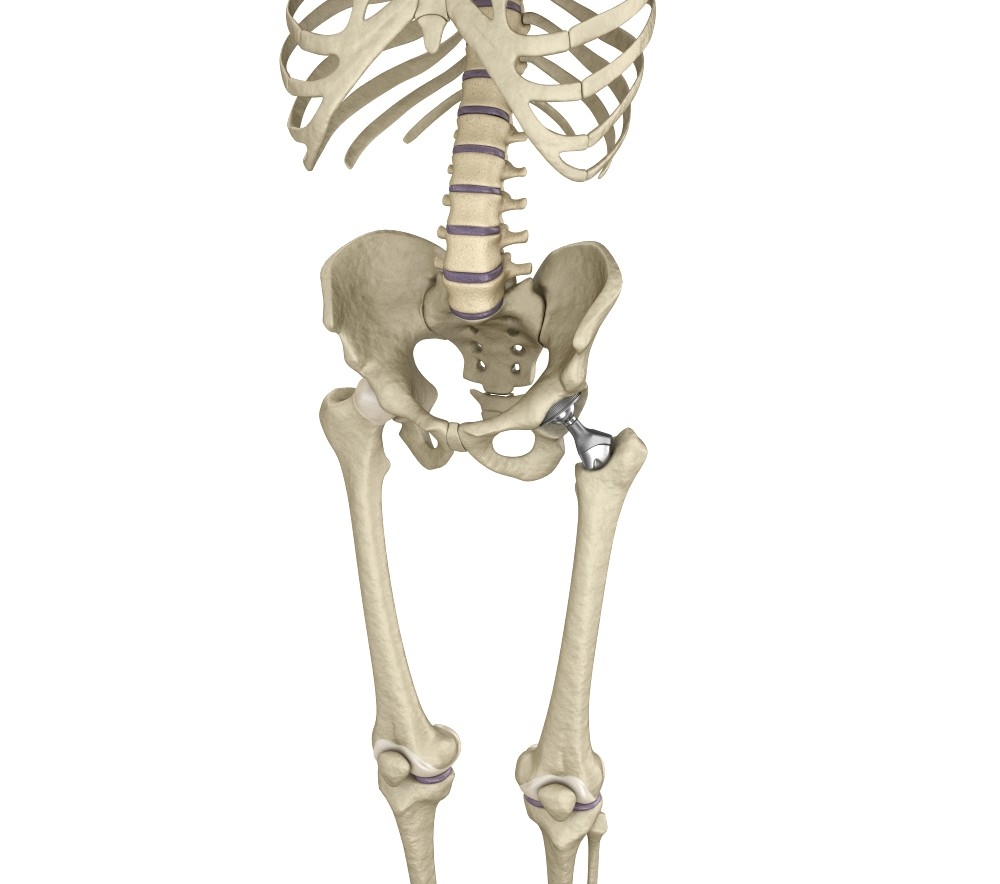

3D Hip Replacement Implant Installed Model - TurboSquid 1220758

www.turbosquid.com

www.turbosquid.com

hip 3d model replacement implant bone installed pelvis turbosquid

3D Hip Replacement Implant Installed Model - TurboSquid 1220758

www.turbosquid.com

www.turbosquid.com

implant turbosquid

3D Hip Replacement Implant Installed Model - TurboSquid 1220758

www.turbosquid.com

www.turbosquid.com

3D Hip Replacement Implant Installed Model - TurboSquid 1220758

www.turbosquid.com

www.turbosquid.com

turbosquid